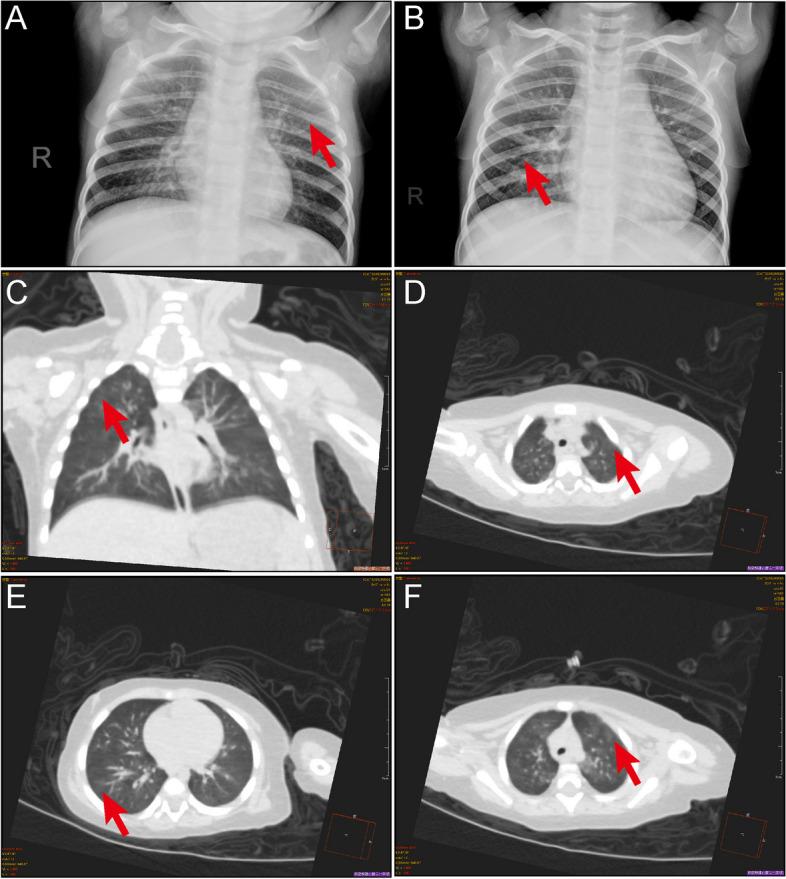

Clinical and epidemiological characteristics of 96 pediatric human metapneumovirus infections in Henan, China after COVID-19 pandemic: a retrospective analysis.

Between April 29 and June 5, 2023, 96 pediatric patients were identified as infected with HMPV with a median age of 33.5 months (interquartile range, 12 ~ 48 months). The majority (87.5%) of infected children were under 5 years old. Notably, severe cases were statistically younger. Predominant symptoms included fever (81.3%) and cough (92.7%), with wheezing more prevalent in the severe group (56% vs 21.1%). Coinfection with other viruses was observed in 43 patients, with Epstein-Barr virus (EBV) (15.6%) or human rhinovirus A (HRV type A) (12.5%) being the most common. Human respiratory syncytial virus (HRSV) coinfection rate was significantly higher in the severe group (20% vs 1.4%). Bacterial coinfection occurred in 74 patients, with Haemophilus influenzae (Hin) and Streptococcus pneumoniae (SNP) being the most prevalent (52.1% and 41.7%, respectively). Severe patients demonstrated evidence of multi-organ damage. Noteworthy alterations included lower concentration of IL-12p70, decreased lymphocytes percentages, and elevated B lymphocyte percentages in severe cases, with statistical significance. Moreover, most laboratory indicators exhibited significant changes approximately 4 to 5 days after onset.